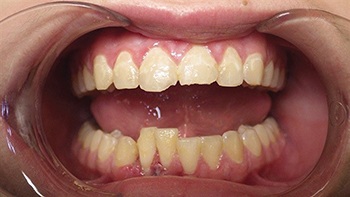

Figs. 3-4: Initial Appointment

Figs. 5-6: One-week follow-up showing early alignment after placement of brackets and light NiTi wire.

Figs. 7-8: Two-week follow-up with continued improvement in positioning and stabilization.